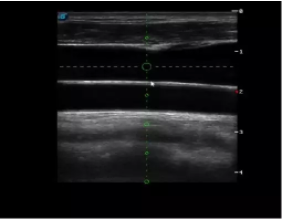

胎移植臨床圖

多數(shù)的生殖科醫(yī)生對(duì)于受精卵的植入采用憑經(jīng)驗(yàn)操作或是使用傳統(tǒng)腔內(nèi)探頭引導(dǎo),同樣存在手術(shù)空間小、受精卵放置位置不確定等風(fēng)險(xiǎn)。專業(yè)的宮腔專用探頭,配合專用的窺器使用,為醫(yī)生提供最大的手術(shù)視野。